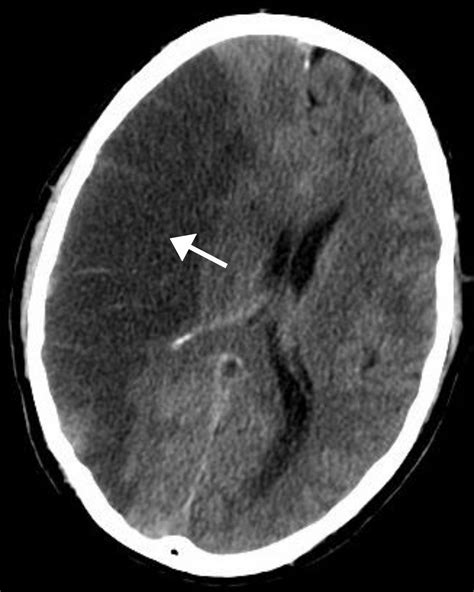

Diagnosing a Left Sided Cerebrovascular Accident involves a series of tests to determine the type and location of the stroke. Common diagnostic tools include:

• CT Scan: A computerized tomography scan to visualize the brain and detect any bleeding or blockages.